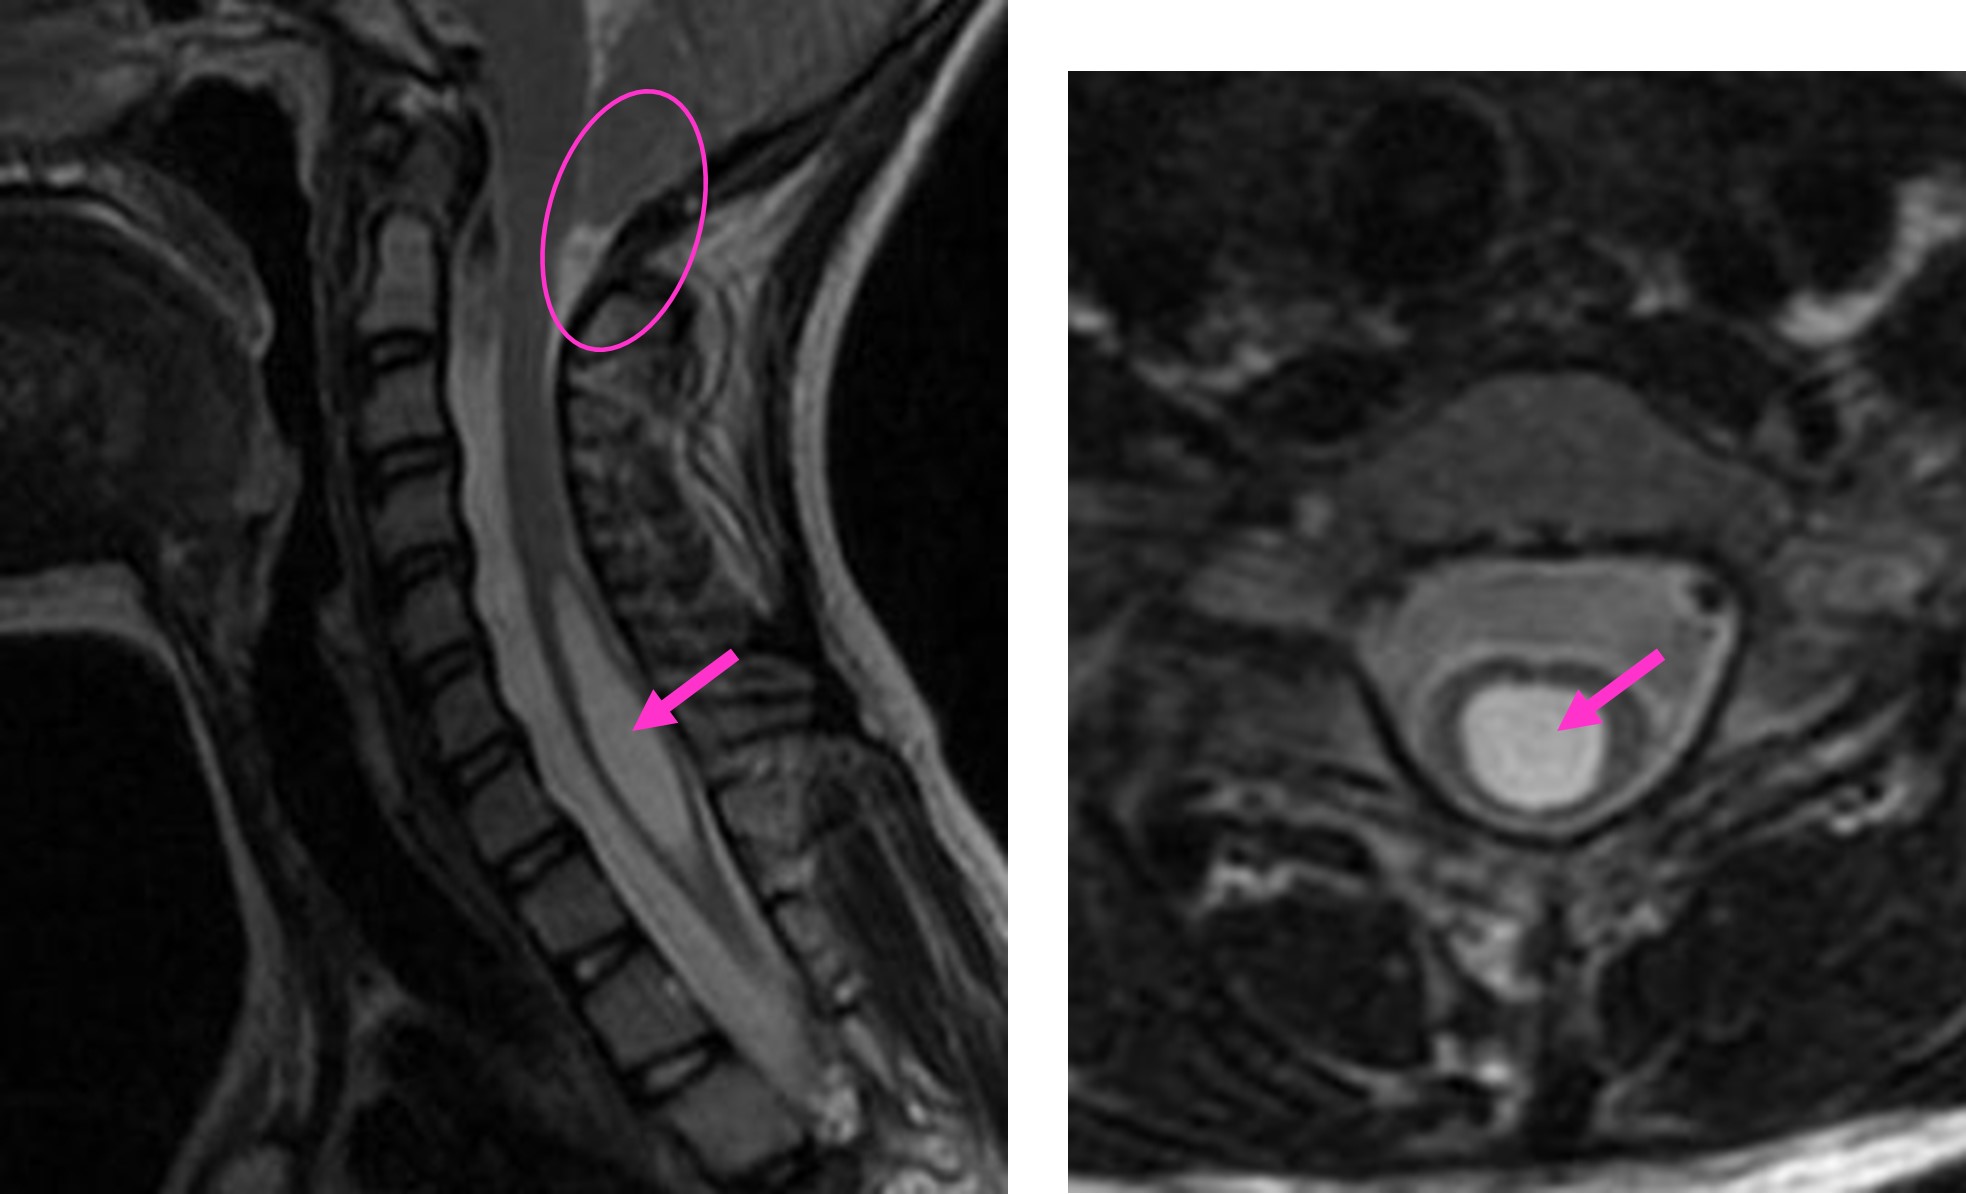

図 アーノルドキアリ奇形

(左)小脳の一部が下方に下垂しています(丸で囲った部分)。アーノルドキアリ奇形により、頚髄には空洞(シリンクス)が形成されています(矢印で示す部分)。

(右)脊髄の横断像では、脊髄の中に空洞(シリンクス)が形成されています(矢印で示す部分)。